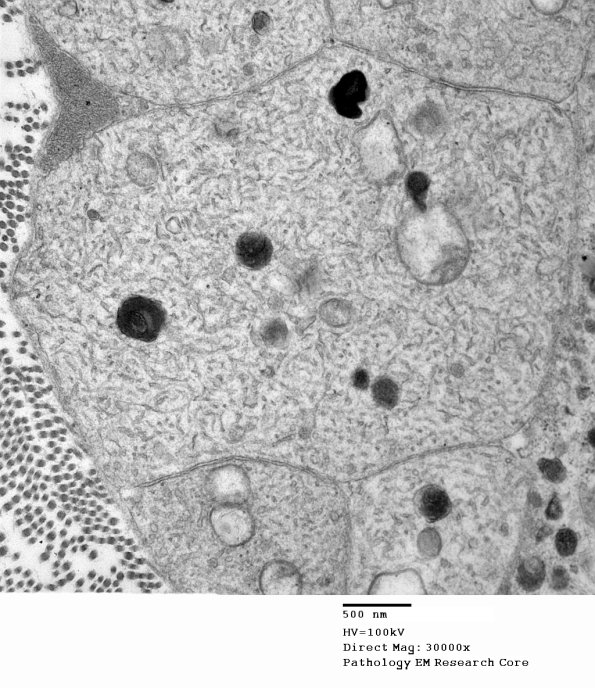

Higher magnification of image 3B7. (electron micrographs)

Washington University Experience | PERIPHERAL NEUROPATHY | 5 AXONAL REGENERATION | 3B7B Axonal regeneration, SLE NP Vasculitis (Case 1)_048 - Copy